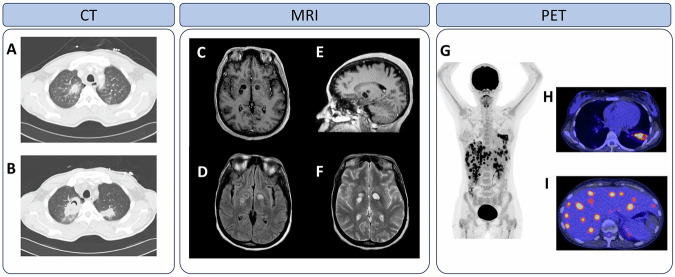

侵袭性真菌疾病(IFDs)提出了一个日益增长的临床挑战,强调迫切需要改进诊断,治疗和机制的理解。这篇综述强调了创新成像技术在所有尺度上的关键作用——从全身水平的诊断和治疗监测到临床和临床前环境中细胞分辨率的宿主-病原体相互作用。这些成像模式有助于将临床前创新转化为临床应用,加速研究并推进IFD管理。

Invasive fungal diseases (IFDs) present a growing clinical challenge, underscoring the urgent need for improved diagnostics, therapeutics and mechanistic understanding. This review highlights the key role of innovative imaging techniques across all scales - ranging from whole-body-level diagnostics and therapy monitoring to host-pathogen interactions at cellular resolution in both clinical and preclinical settings. These imaging modalities facilitate translation of preclinical innovations into clinical applications, accelerating research and advancing IFD management.